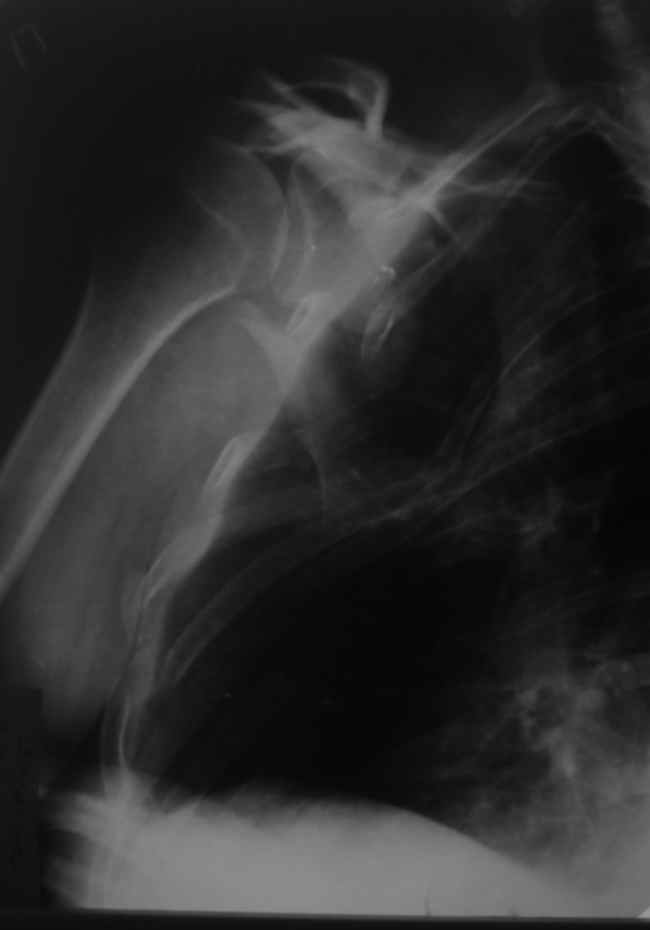

Перелом лопатки, ключицы, ребер |

Уважаемые коллеги, помогите определиться с тактикой. Больной 1953гр, травма на стройке, придавило тяжелым

предметом.

Сейчас в сознании, стабилен, плевральная полость задренирована. Предполагаем синтез ключицы, если бы не переломы ребер, установили бы шину ЦИТО.

Есть у кого опыт открытого/закрытого синтеза подобной лопатки? Что делать с клювовидным отростком?